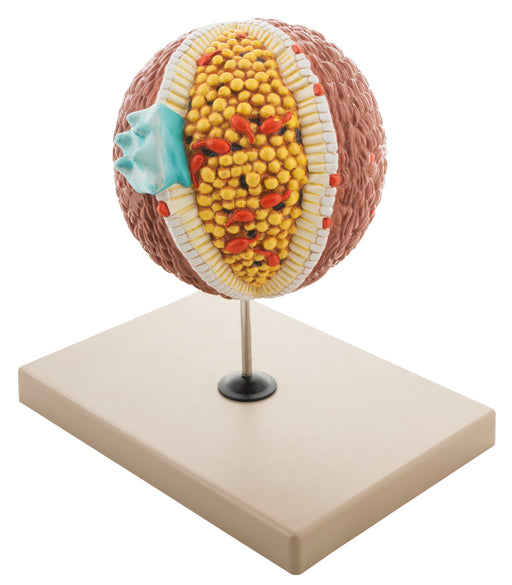

Cholesterol

Cholesterol is a waxy substance that comes from two sources: your body and food. Your body, and especially your liver, makes all the cholesterol yo...

View full detailsAM16037 -